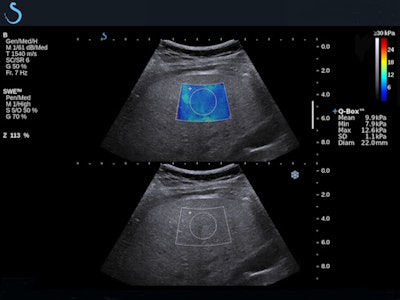

Evaluating liver stiffness

Over the past decade, several studies have demonstrated the benefits of SWE for assessing liver stiffness quantitatively, noninvasively, and accurately.7 SWE has been shown to yield accurate diagnostic measurement of liver fibrosis in a range of patients, from hepatitis C patients to cirrhosis, including those with ascites.8

One of the more recent studies found the moving images obtained this way accurately measured incidentally discovered liver lesions in patients with no history of liver disease; another found that SWE aided the detection of portal hypertension, a dangerous complication of cirrhosis.9 Two-dimensional images obtained noninvasively were especially important for monitoring the progression of liver disease in vulnerable patient populations such as those suffering from chronic viral hepatitis.